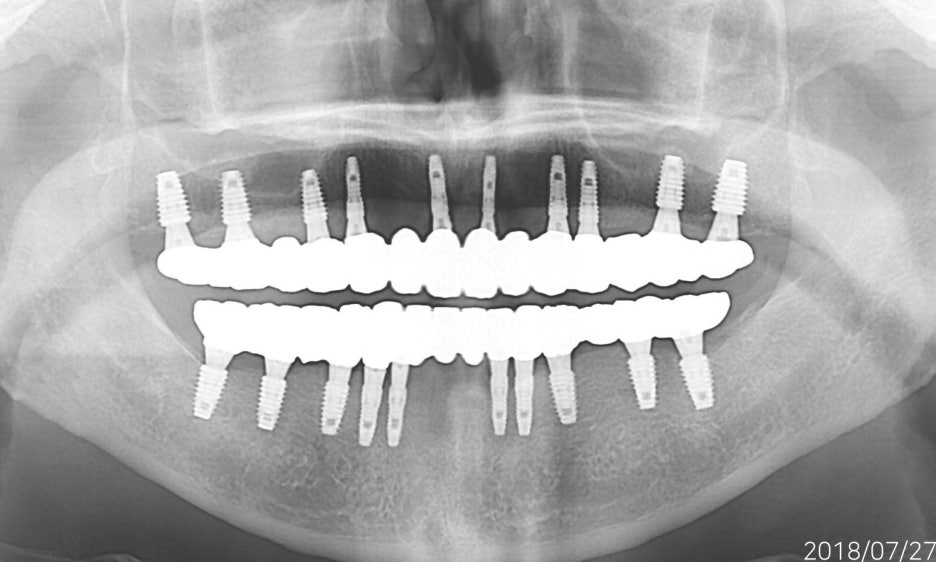

무치악환자를 위한 전악임플란트

전악임플란트 중점 치료

<참고이미지> 무치악 환자의 임플란트 치료 사례 / 환자에 따라 치료결과는 다를 수 있으며 임플란트 주위염 등이 발생할 수 있습니다.

무치악 환자에게 적용시 치아의 기능을 일정수준으로 회복할 수 있는 치료입니다.

<치료의 이해를 돕기위한 참고이미지>

20.09.19 경과체크 / 무치악 임플란트 치료 / 환자에 따라 치료결과는 다를 수 있으며 임플란트 주위염 등의 부작용이 발생할 수 있습니다.

기능의 회복은 물론 심미적인 목적도 충족 시킬 수 입니다.

치아의 상태와 잇몸뼈 상태를 고려한 식립

필요한 개수만큼 식립하여 경제적으로 치료 받을 수 있습니다.